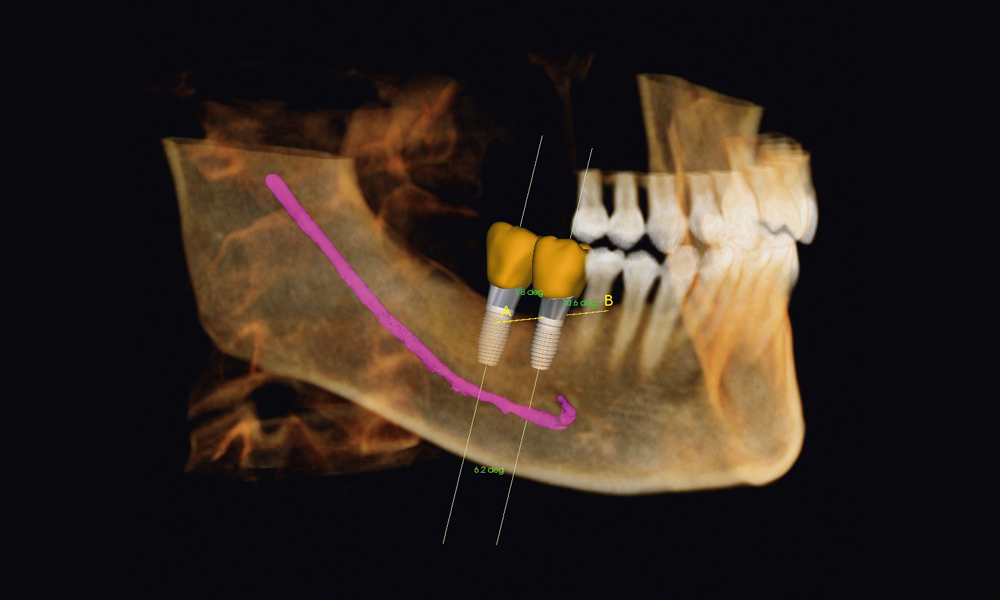

Our centre utilizes state-of-the-art 3D cone-beam CT (computed tomography) technology that provides highly accurate 3-D radiographic images for the diagnosis, planning and treatment of oral surgery.

This technology provides highly accurate 3D radiographic images for the diagnosis, planning and treatment of dental implantology, TMJ analysis, airway assessment, oral and orthognathic surgery and other dental procedures.

Undistorted, anatomically correct views of the jaws, teeth and facial bones along with cross-sectional (bucco-lingual), axial, coronal, sagittal, cephalometric and panoramic views are easily generated.

Three-dimensional images enable a level of anatomical accuracy and patient care not possible with 2-D technologies. With the addition of cone-beam CT technology in our office, our practice is committed to providing innovative, high-quality, patient care.